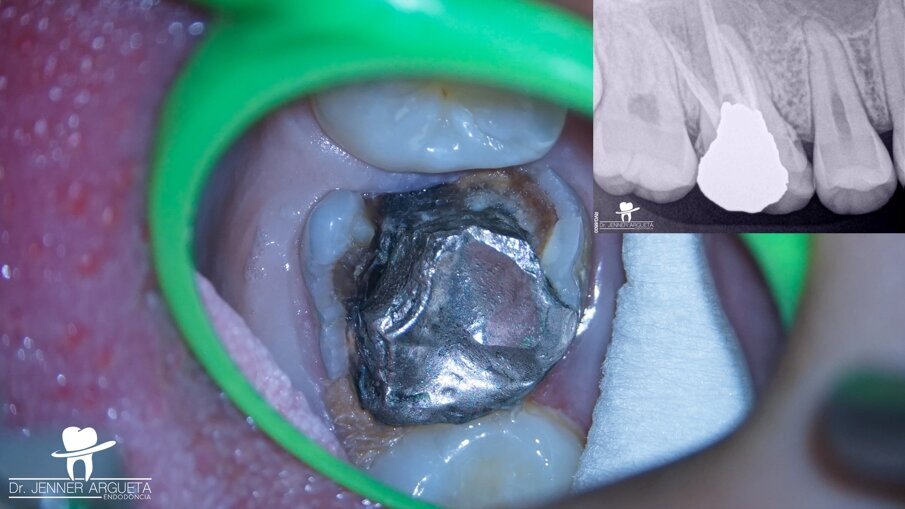

A 16-year-old female patient was referred to the office for evaluation of tooth #16 (Fig. 1). The referring dentist asked that we apply all the available resources to save the tooth. The diagnosis was previously treated and symptomatic periapical periodontitis. After detailed examination, it was concluded that the tooth was not restorable. With the parents’ and patient’s agreement, we decided on an autogenous transplantation of tooth #18 to the site of tooth #16 after its extraction (Fig. 2). The orthodontist had determined that tooth #18 was to be extracted, and it was intended that the patient’s occlusion should be balanced by the end of the orthodontic treatment. Teeth #16 and 18 were extracted in the least traumatic way possible. After minor bone remodelling of the socket using low-speed burs, the third molar was transplanted to the recipient site (Fig. 3). A nylon monofilament flexible splint was used to keep the tooth in place (Fig. 4). Fifteen days later, the splint was removed, healthy soft tissue was observed, the patient was asymptomatic, and the tooth was stable in the site (Figs. 5a & b).

Fig. 1: Severely destroyed maxillary first molar with an old amalgam restoration, previous root canal therapy and recurrent caries.

Fig. 2: Periapical radiograph of the maxillary right molar. Tooth #18 was to be transplanted to the site occupied by tooth #16.